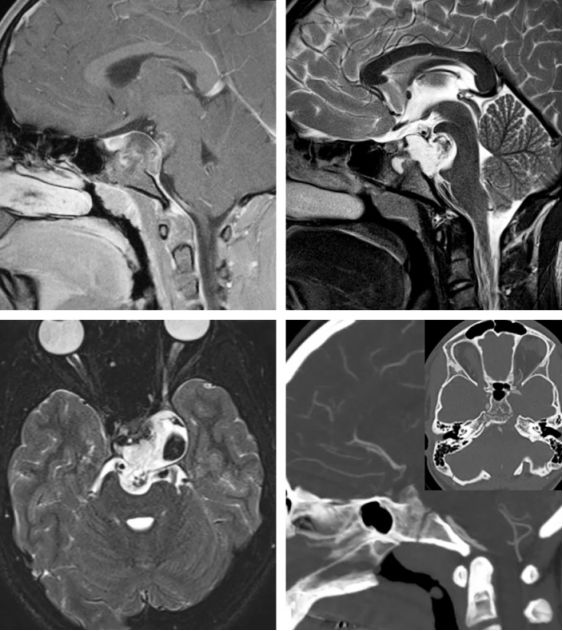

图1:向硬膜下生长的斜坡脊索瘤。肿瘤在T1加权相表现为等低信号,局部高信号(肿瘤内出血或粘液囊肿),在T2加权相表现为高信号。需注意增强相的不均匀强化表现。CT上表现为骨质破坏性改变,有时可伴边缘硬化。相对于周围的脑组织肿瘤呈等高密度。

图2:软骨肉瘤(黄色箭头)表现为不均匀强化,在T2加权相表现为高信号。CT上与脊索瘤不同,软骨肉瘤更易向一侧生长且骨质边缘处侵蚀迹象较少。